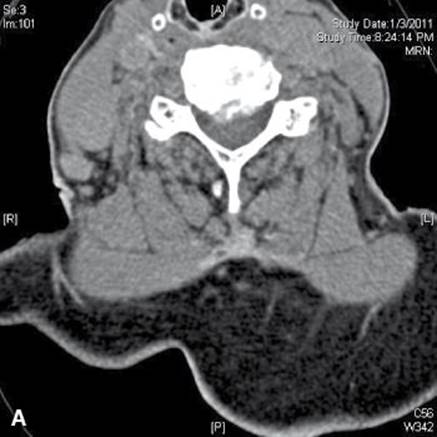

c. CT scan (Fig. 22.3A, B). It shows better bone detail than MRI, but is not as good at showing the neural structures. The two studies together are ideal for this group of patients, but this is obviously not cost effective, so MRI is the first choice.

FIGURE 22.3 Axial CT with soft tissue (A) and bone windows (B) demonstrating moderate to severe central canal stenosis secondary to an eccentric disc protrusion (C5–C6) as well as osteophyte with foraminal stenosis.